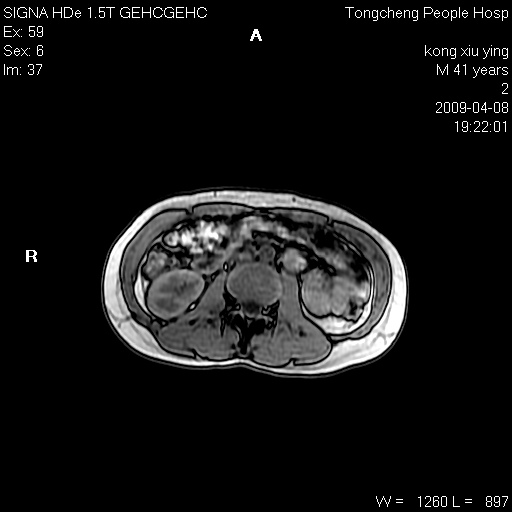

标题: CL1008:【经典】胆囊石榴籽样结石。 [打印本页]

标题: CL1008:【经典】胆囊石榴籽样结石。

女,41岁。健康体检——彩超提示:胆囊显示不清。平素健康,无不适感。

腹部mr扫描及mrcp,图像如下: